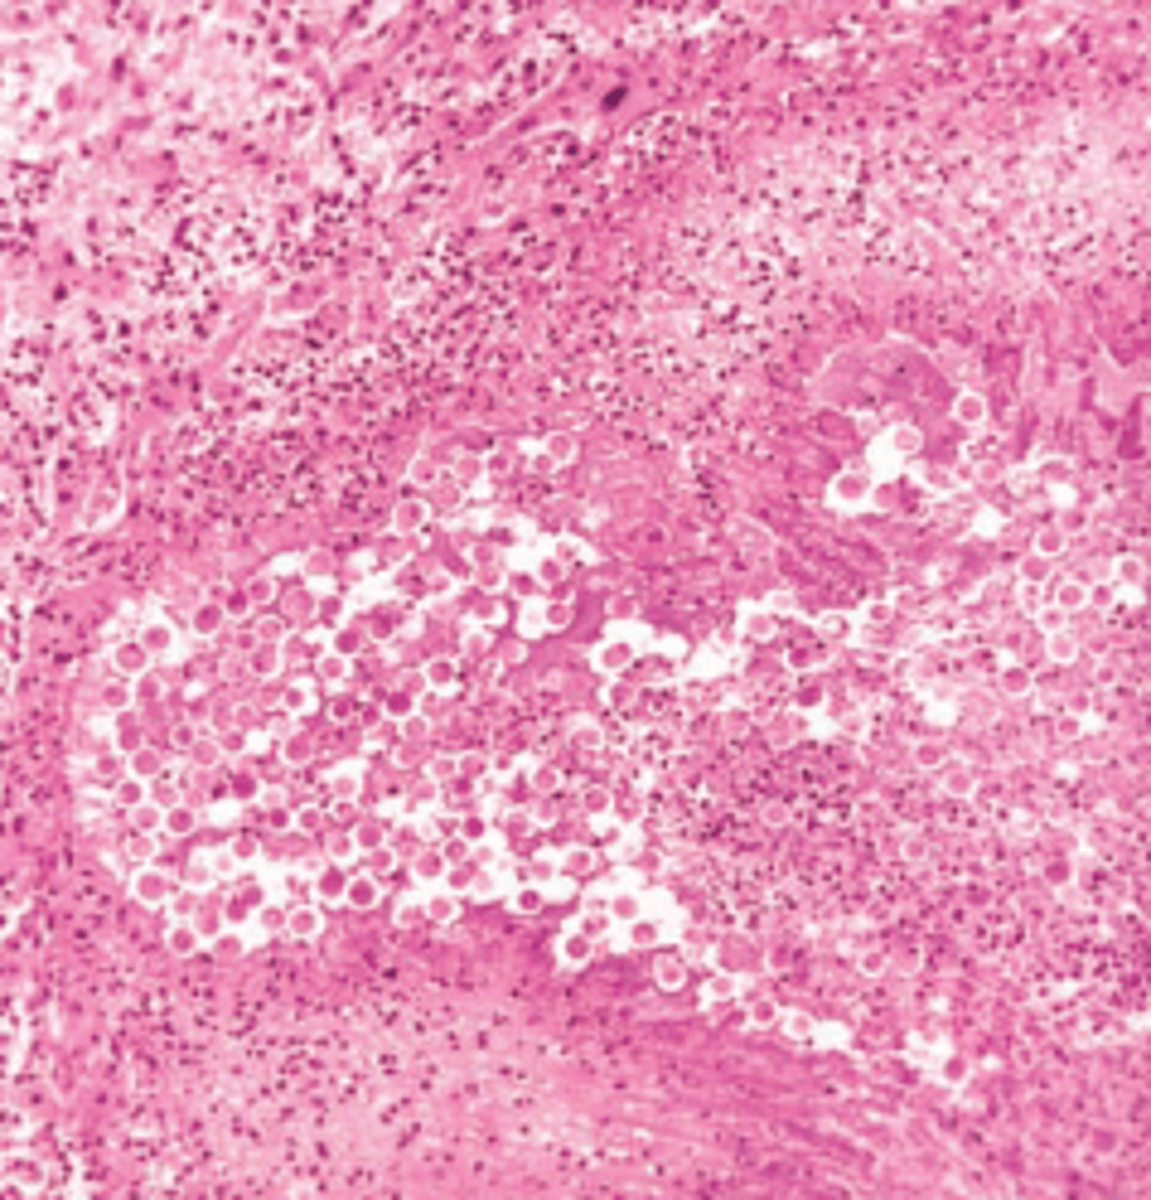

Amebic liver abscess

A 30-year-old man from Mexico presents with a 3-week history of constant pain in his upper right quadrant and epigastrium and persistent cough. The patient also reports a recent history of nausea, vomiting, and bloody diarrhea. Physical examination shows hepatomegaly and tenderness over the right upper quadrant. A liver biopsy displays fibroblastic proliferation and trophozoites (shown in the image). Which of the following is the most likely diagnosis?

(A) Amebic liver abscess

(B) Cystic hydatid disease

(C) Hepatic malaria

(D) Pyogenic liver abscess

(E) Weil disease